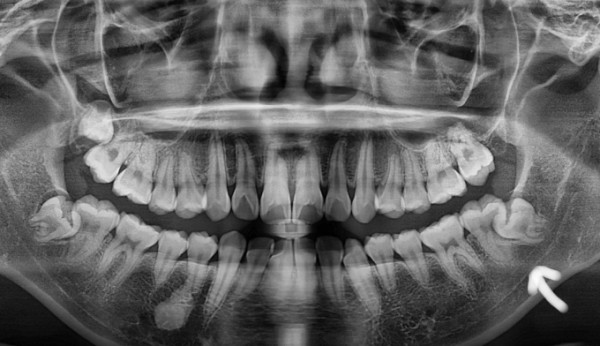

지금 섣불리 교정치료를 시작하기 보다, 뿌리가 녹아버린 어금니를 뽑고 사랑니가 맹출되기를 기다렸습니다.

약 1년 뒤, 사랑니가 어금니 자리를 멀쩡하게 대체할 수 있게 잘 올라와주었습니다,